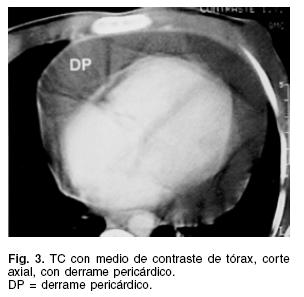

En dos (9.5%) el derrame pericárdico se asoció a la presencia de derrame pleural, y en uno (4.7%) había evidencia de infiltrado pulmonar apical derecho. El electrocardiograma cursó con anormalidades del segmento ST y ondas T invertidas en 80.9% de los pacientes, el resto no mostró cambios específicos. El ecocardiograma transtorácico identificó en todos los casos cavidades cardíacas en diámetros normales, con la presencia de derrame pericárdico. En 12 (57.1%) el derrame era de moderada cantidad, y 9 (42.8%) tenían un gran derrame pericárdico (Fig. 2). Hubo evidencia de engrasamiento pericárdico, con formación de puentes filamentosos y adherencias lineales en 7 de ellos. Existieron signos ecocardiográficos de taponamiento en 42.8% de los casos, que incluyeron compresión de cavidades derechas, dilatación de vena cava y variación respiratoria en las velocidades Doppler a través de las válvulas tricúspide y mitral. La tomografía computada de tórax se realizó en 15 pacientes. En todos hubo evidencia de derrame pericárdico (Fig. 3), 4 (26.6 %) casos tenían engrasamiento pericárdico, en uno había derrame pleural derecho y en otro un infiltrado parenquimatoso apical derecho.